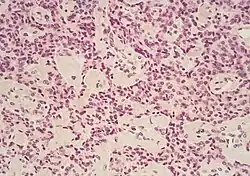

The most common form of pancreatic cancer (adenocarcinoma) is typically characterized by moderately to poorly differentiated glandular structures on microscopic examination. There is typically considerable desmoplasia or formation of a dense fibrous stroma or structural tissue consisting of a range of cell types (including myofibroblasts, macrophages, lymphocytes and mast cells) and deposited material (such as type I collagen and hyaluronic acid). This creates a tumor microenvironment that is short of blood vessels (hypovascular) and so of oxygen (tumor hypoxia).[2] It is thought that this prevents many chemotherapy drugs from reaching the tumor, as one factor making the cancer especially hard to treat.[2][3]

| Cancer type | Relative incidence[11] | Microscopy findings[11] | Micrograph | Immunohistochemistry markers[11] | Genetic alterations[11] |

| Pancreatic ductal adenocarcinoma (PDAC) | 90% | Glands and desmoplasia | ![]() |